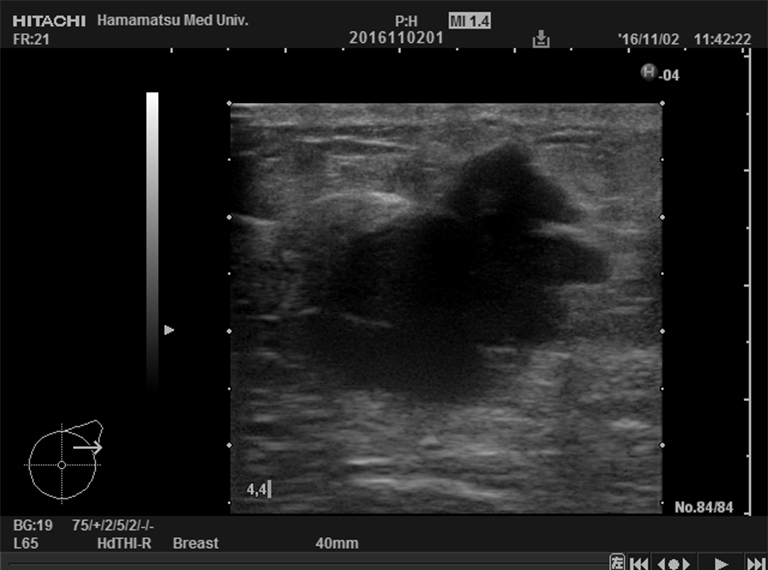

■腫瘍の位置

■腫瘍の超音波画像(中央の黒い影が腫瘍)

化学療法前

26×28×21 mm

3週間後

26×22×17 mm

6週間後

18×16×10 mm